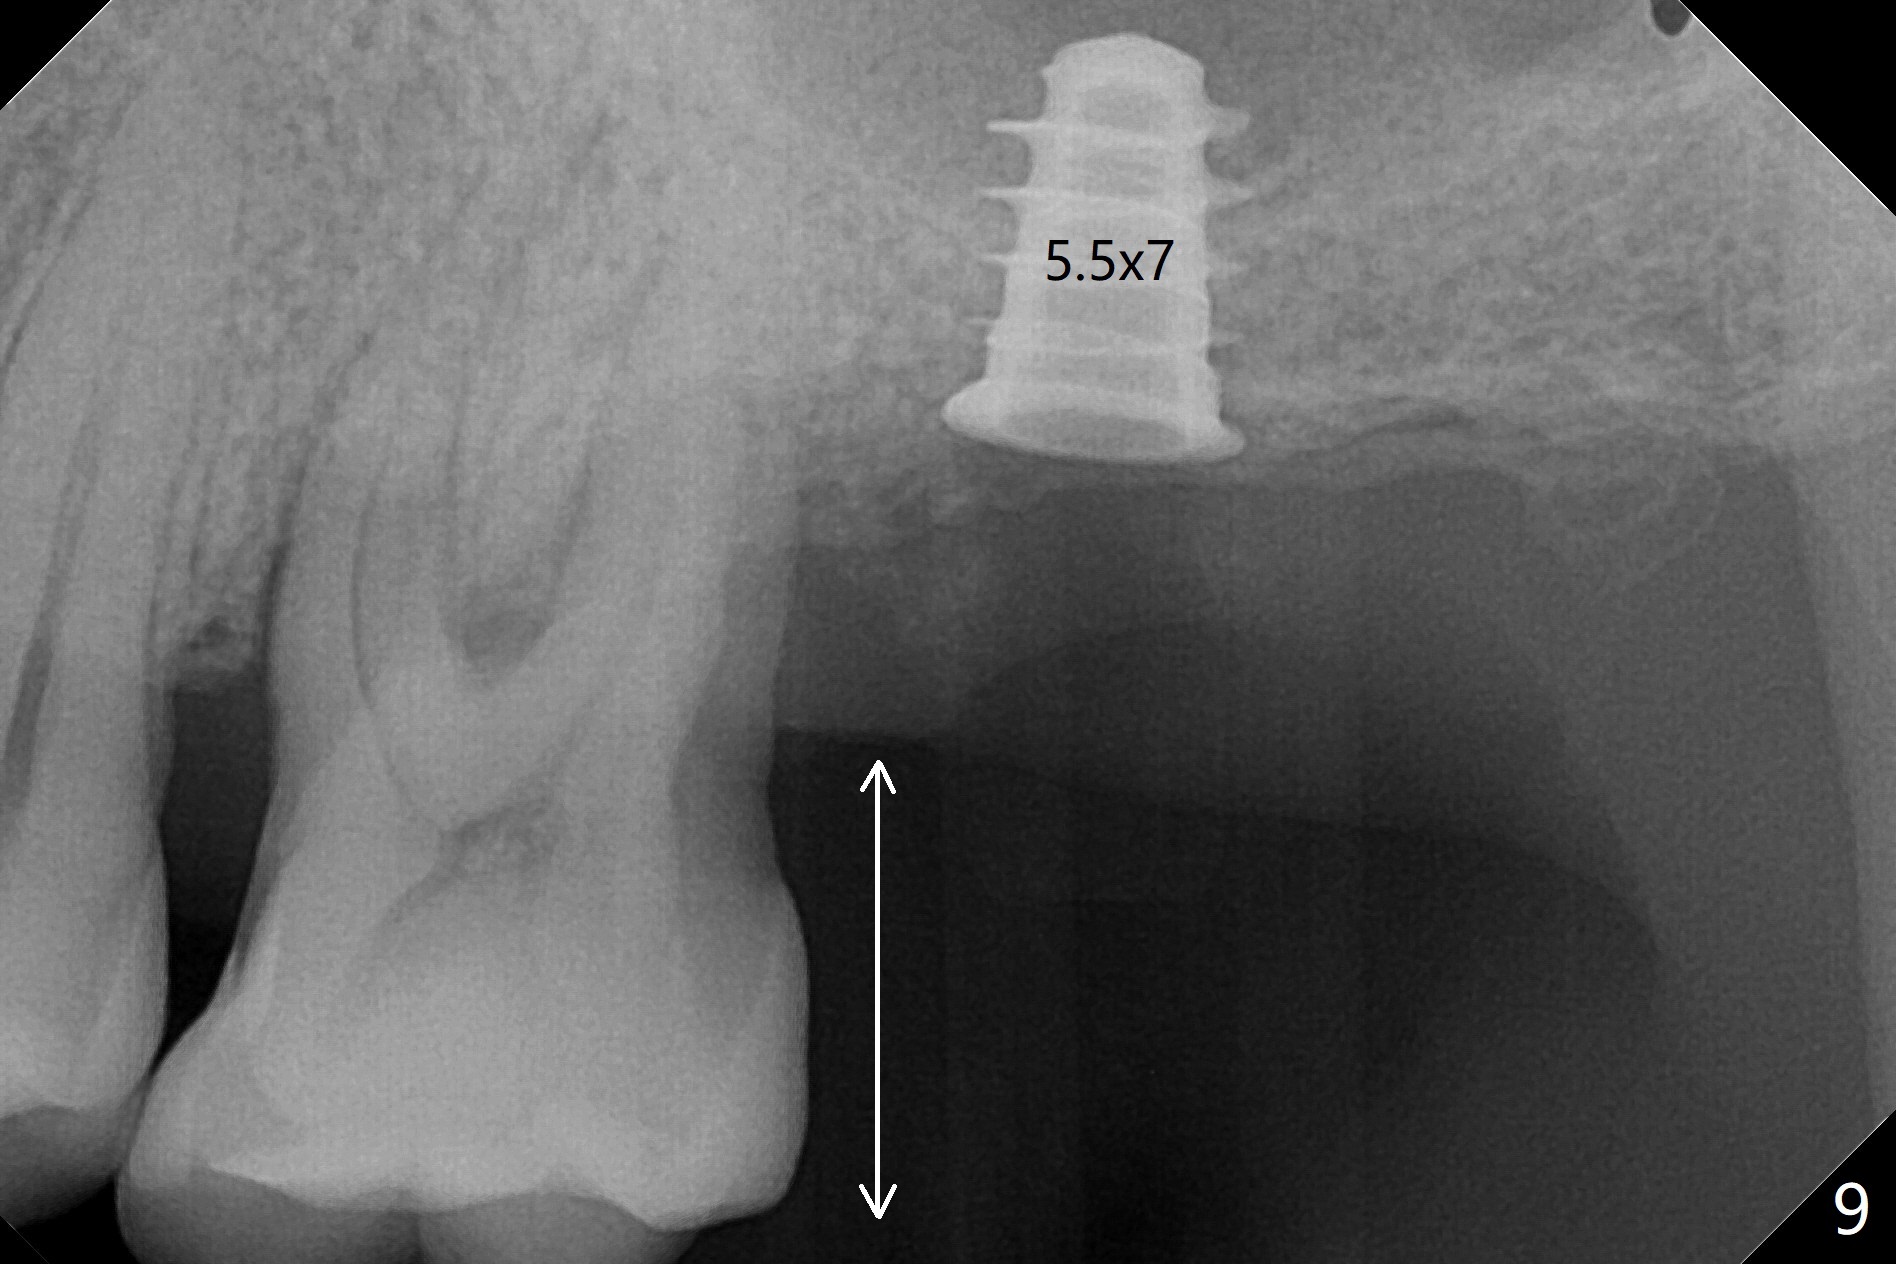

Bone在上颌窦里凝固了。其实左侧上颌窦粘膜术前增厚(图四,五:L),人工骨仿佛弥撒在上颌窦膜中(图六)。术后一周病人没有任何鼻窦症状。术后4.5月旋转愈合基台时,病人感到疼痛,终止取模(图七),两个月后复诊,做progressive loading。术后5.5月旋转愈合基台时,植体一起出来,但是上颌窦膜没有破,放置大一号植体(报废)扭力不够(图八),再大一号扭力可以(图九),放置愈合帽。由于邻牙长(图九:双箭头),牙周敷料逗留三周不掉(图十:P)。撤除后,伤口愈合正常。The